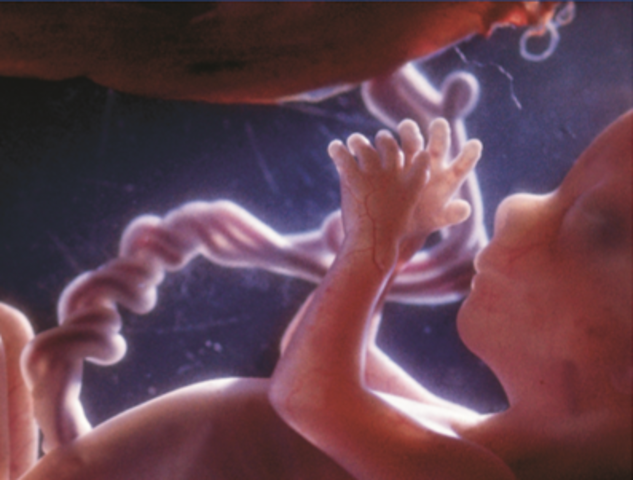

• El 4. o mes 14. a- 15. a semana

El 4. o mes 14. a- 15. a semana

Empieza a desarrollarse el sentido del tacto: ya se han formado los receptores de la sensibilidad cutánea de los dedos. El aparato gustativo también empieza a funcionar y el feto se familiariza con el sabor del líquido amniótico en el que flota y que absorbe por la piel o tragándolo. La cabeza tiene un aspecto menos desproporcionado con respecto al resto del cuerpo. Las manos están completamente formadas.

• 16.a-18.a semanas

La piel ya no es tan fina, aunque sigue siendo transparente y deja ver los vasos sanguíneos. El cabello crece. Los músculos se fortalecen y los movimientos son más vigorosos: la madre empieza a sentirlos. Pero el esqueleto todavía no está osificado del todo. Para muchos padres, gracias a la eco grafía este 4.º mes es también el momento de una revelación: pueden ver a ese hijo. Al final de este 4.º mes, el feto mide casi 20 cm y pesa 250 g.